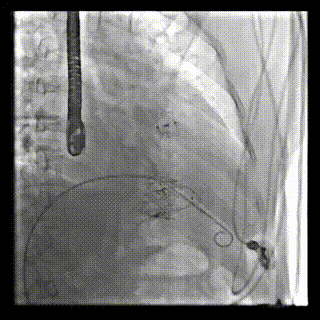

本周三例接受LuX-Valve Plus經(jīng)血管三尖瓣置換術(shù)的患者中,第一例患者為冠狀動脈旁路移植術(shù)+Bentall+二尖瓣成形術(shù)后;第二例患者為永久起搏器植入術(shù)后,存在跨三尖瓣導(dǎo)線;第三例患者合并房顫、房缺及左心耳封堵術(shù)后。

三例患者入院后,葛均波院士團(tuán)隊周達(dá)新教授、潘文志教授、張源博士、陳莎莎博士及心超室的潘翠珍教授、李偉教授對患者的情況進(jìn)行詳細(xì)評估和討論,最終決定為三例患者選擇LuX-Valve Plus40mm、50mm和50mm型號的瓣膜進(jìn)行手術(shù)治療。手術(shù)后即刻拔除氣管插管,術(shù)后患者三尖瓣反流癥狀得到顯著改善,復(fù)查心超結(jié)果顯示人工三尖瓣瓣膜支架固定穩(wěn)定,瓣葉關(guān)閉形態(tài)未見異常,未見明顯反流。

LuX-Valve Plus是LuX-Valve系列產(chǎn)品的第二代,采用的是經(jīng)血管入路的全新輸送系統(tǒng),其設(shè)計開發(fā)過程得到了上海中山醫(yī)院葛均波院士及其團(tuán)隊的精心指導(dǎo),研究結(jié)果提示瓣膜植入的安全性和有效性俱佳,尤其瓣膜獨特的設(shè)計使其具有極佳自適應(yīng)性,本周三例患者病因及解剖結(jié)構(gòu)各具特點,但均可從LuX-Valve Plus植入術(shù)明顯獲益。目前,LuX-Valve Plus已在全國各中心開展救治性臨床研究,相信未來定會為更多的三尖瓣反流患者帶來福音。